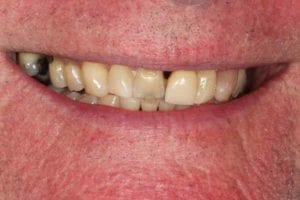

Full Mouth Rehabilitation

Full mouth Treatment – missing upper front teeth and mispositioned implants in the Lower left side meant planning was key here to get the desired result. Implants were placed to replace the missing teeth, veneers/crowns on the remaining upper teeth allowing an improvement in overall shape and colour, and the implant crowns on the lower left were change to bring into the line of the bite.